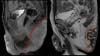

The imaging results include fistulas, granulomas, abscesses, scar bridges, and dermal and subcutaneous thickening of well-delimited borders6. Abscesses are characterized by circumferential morphology in the subcutaneous tissue, with a low signal in T1 and high in T2, with evident contrast enhancement due to the contrast medium and restricted diffusion (Figures 1 to 3). Fistulas in the subcutaneous and dermal tissues of the anal canal and the distal part of the rectum can mimic Crohn’s disease or cryptoglandular disease. These diseases can also coexist with HS, which impairs the ability to determine a diagnosis6,7.

The most important imaging methods for the assessment of HS include Doppler ultrasonography and magnetic resonance imaging. MRI is particularly relevant in more severe cases of the disease and is a useful technique to establish a diagnosis for HS, determine the extent of the lesion, and plan the optimal therapeutic management. MRI results are relatively nonspecific, with thickening of dermal and subcutaneous tissues, with low intensity signal in T1 and high in T2 and STIR. However, the presence of these findings together with fistulas, sinus tracts, and scars, especially in the anal canal, are highly suggestive of HS.